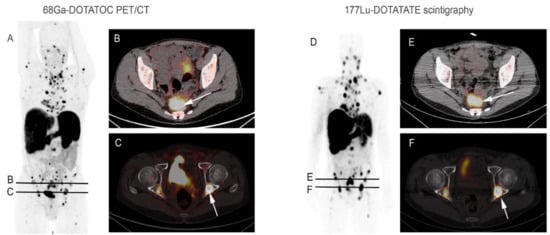

Figure 1. A 65-year-old man with metastatic well-differentiated grade 2 rectal neuroendocrine tumor, progressive after chemotherapy, addressed for PRRT. 68Ga-DOTATOC PET/CT maximum intensity projection image (A) and axial fused PET/CT images (B,C) showed high multiple focal uptakes, corresponding to mediastinal, abdominal lymph nodes, liver and bone lesions ((C) arrow: example of bilateral cotyle posterior wall lesions) associated with a large rectal lesion ((B) arrow). Post 177Lu-DOTATATE therapy whole-body image (D) after the first administration showed focal tracer uptake in all lesions correlating with 68Ga-DOTATOC PET/CT images, as observed in fused SPECT/CT images (E,F).